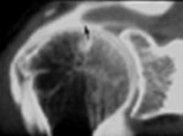

LES RADIOGRAPHIES SIMPLES

On utilisera le plus fréquemment des incidences de face sous plusieurs rotations (rotation interne, rotation zéro, rotation externe), et certaines incidences de profil, différentes selon l’origine de la pathologie (profil axillaire, ou encore profil de glène).